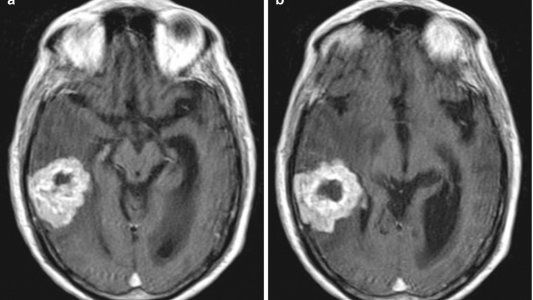

El juez Claudio Bonadio tenía 64 años y padecía, desde hace poco más de un año, de un glioblastoma multiforme, el tipo de tumor cerebral más agresivo que existe.

El glioblastoma es un tumor muy poco frecuente y según las estadísticas se dan dos casos cada 100 mil habitantes al año, pero su grado de daño es letal por ser de los más malignos .

A diferencia de otros tumores, tiene un crecimiento muy rápido y puede desarrollarse a cualquier edad, aunque principalmente afecta a los adultos de entre los 45 y los 70 años.